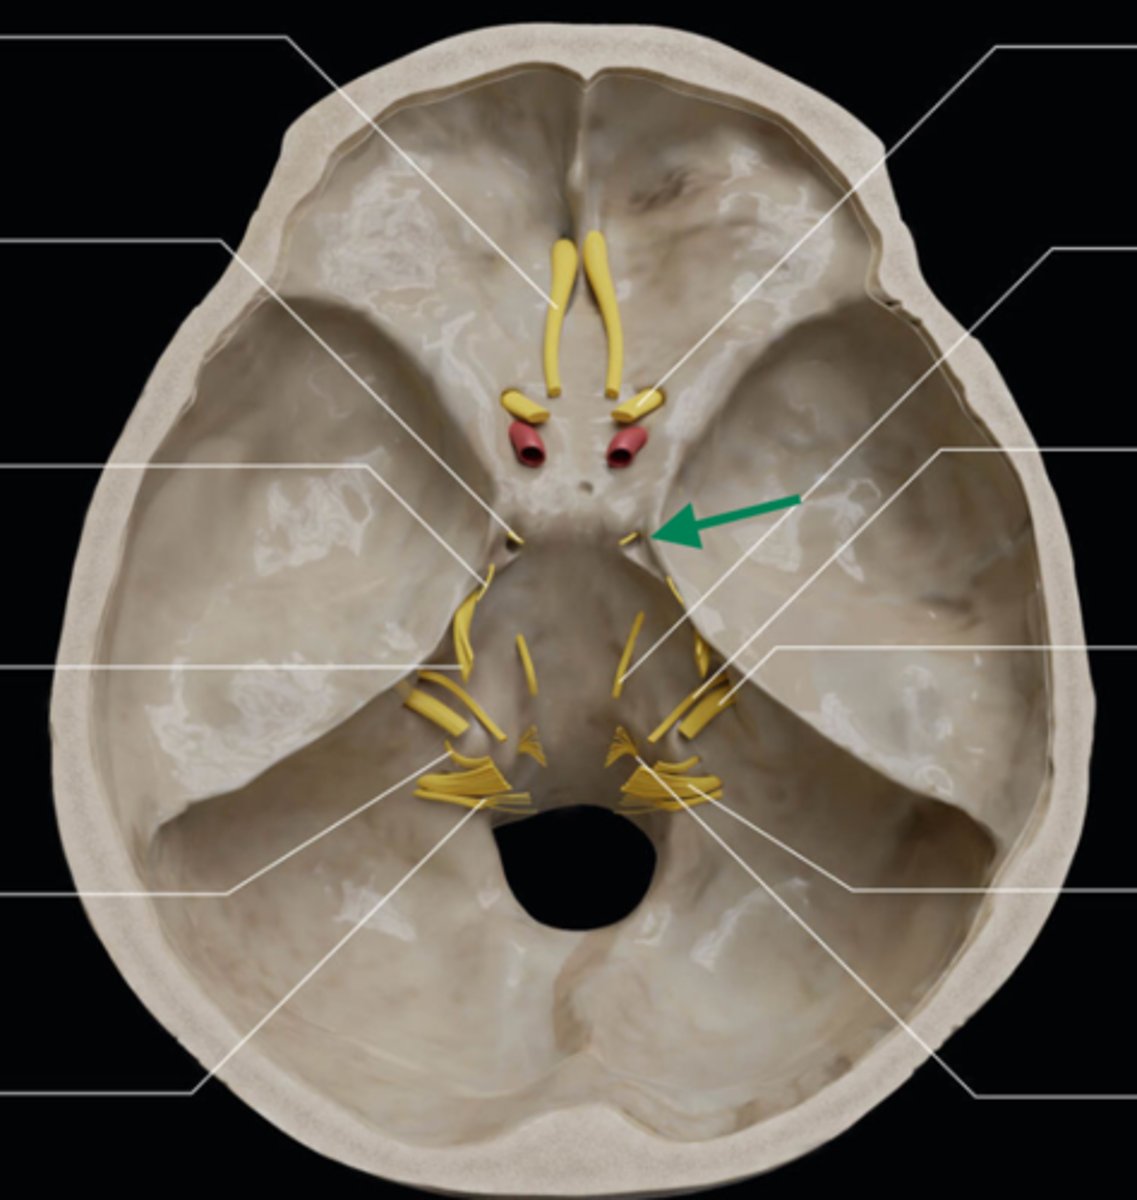

olfactory bulb

olfactory tract

optic nerve (CN II)

internal carotid artery

oculomotor nerve (CN III)

trochlear nerve (CN IV)

abducent nerve (CN VI)

trigeminal nerve (CN V)

facial nerve (CN VII)

vestibulocochlear nerve (CN VIII)

glossopharyngeal nerve (CN IX)

vagus nerve (CN X)

accessory nerve (CN XI)

hypoglossal nerve (CN XII)

optic chiasm

trigeminal ganglion

anterior cranial fossa